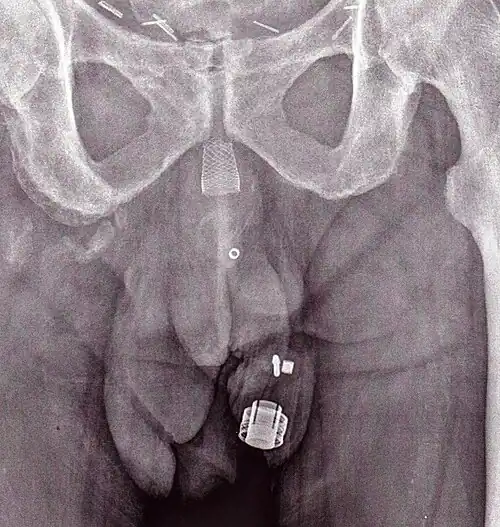

Uma imagem de raio X de um ZSI 375 implantado. O aparelho está desativado - a mole está comprimida abaixo do topo do cilinder. O paciente está continente.

Uma radiografia x de um ZSI 375. O aparelho se encontra ativado - a mola é descomprimida no topo do cilindro. O paciente está continente.